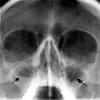

Sinusurile sunt cavitati in osatura faciala a craniului, captusite cu mucoasa. Raceala si sinuzita au la origine acelasi virus, dar sinuzita reprezinta o complicatie. Despre glaucom si tratamentul laser al acestuia, cu dr.

Sinuzita reprezinta o inflamatie a sinusurilor paranazale si poate sa apara la persoane de toate varstele. Acum, să încercăm să ne dăm seama ce se întâmplă în acest proces patologic. Microparticulele de sare uscata cu caracteristici controlate emise de saltmed actioneaza astfel in cazul pacientilor cu sinuzita